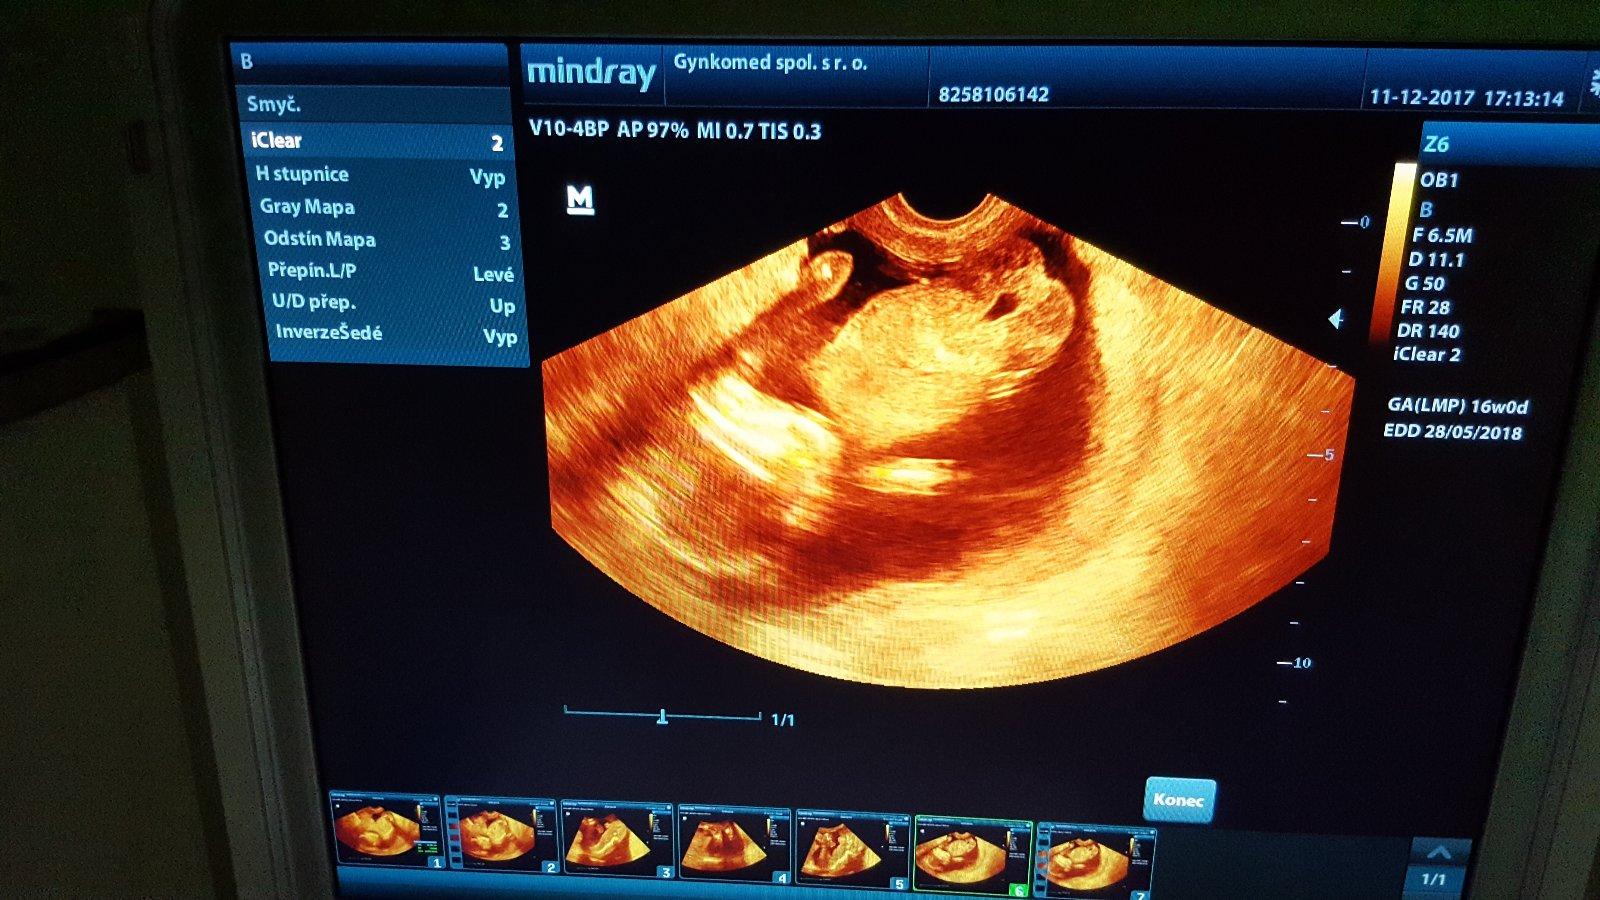

@linee byla jsem minuly tyden 21+0 tt a doktor me vytocil...rikal,ze je to na ueceni jeste brzy a musim.si pockat 😡 mel blbou naladu a plnou cekarnu pupkatych mamin co cekaly na ultrazvuk...objednala jsem.se do Plzne na genetiku a 3D ultrazvuk...takte 13.12.uz snad budu vedet a pisnu jestli holka nebo kluk 😉

Holky tak po dnesnim 3D ultrazvuku to bude holcicka 😍 a je stejna jako jeji starsi sestricka 😊